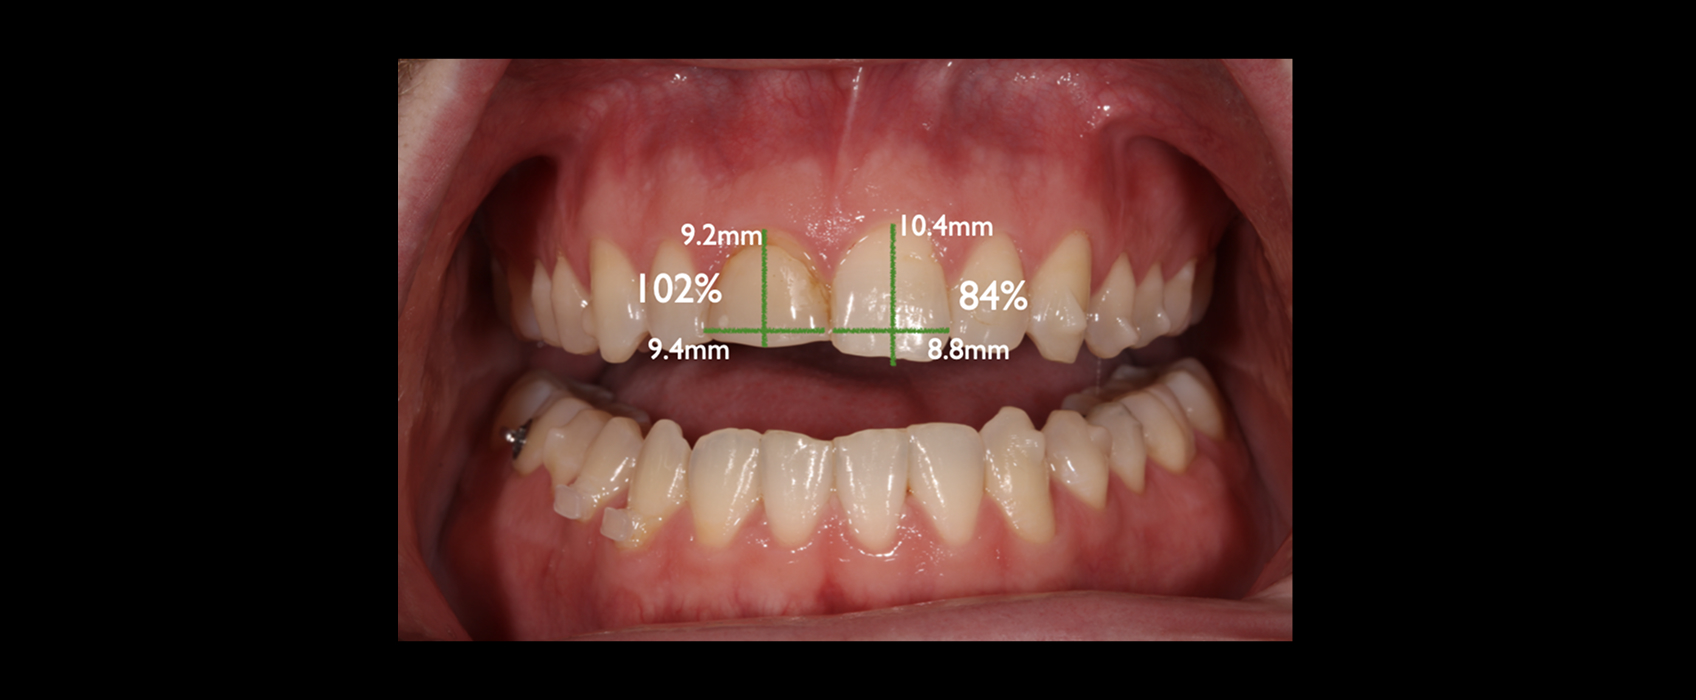

Zach, a patient in his mid-20s, came to our office seeking options for improving his upper front teeth, specifically the noticeable differences in size, shape, and shade between teeth #8 and #9. A childhood bicycle accident had left #8 chipped, and multiple composite restorations over the years hadn’t given him the esthetics he hoped for.

Taking an FGTP approach quickly revealed why restoring #8 had been so challenging. A crossbite was limiting available restorative space, and the gingival position of #8 was more coronal than #9, suggesting supereruption after the original trauma.

Once the teeth were in their proper positions, we could address #8 and #9 with a single crown and veneer.